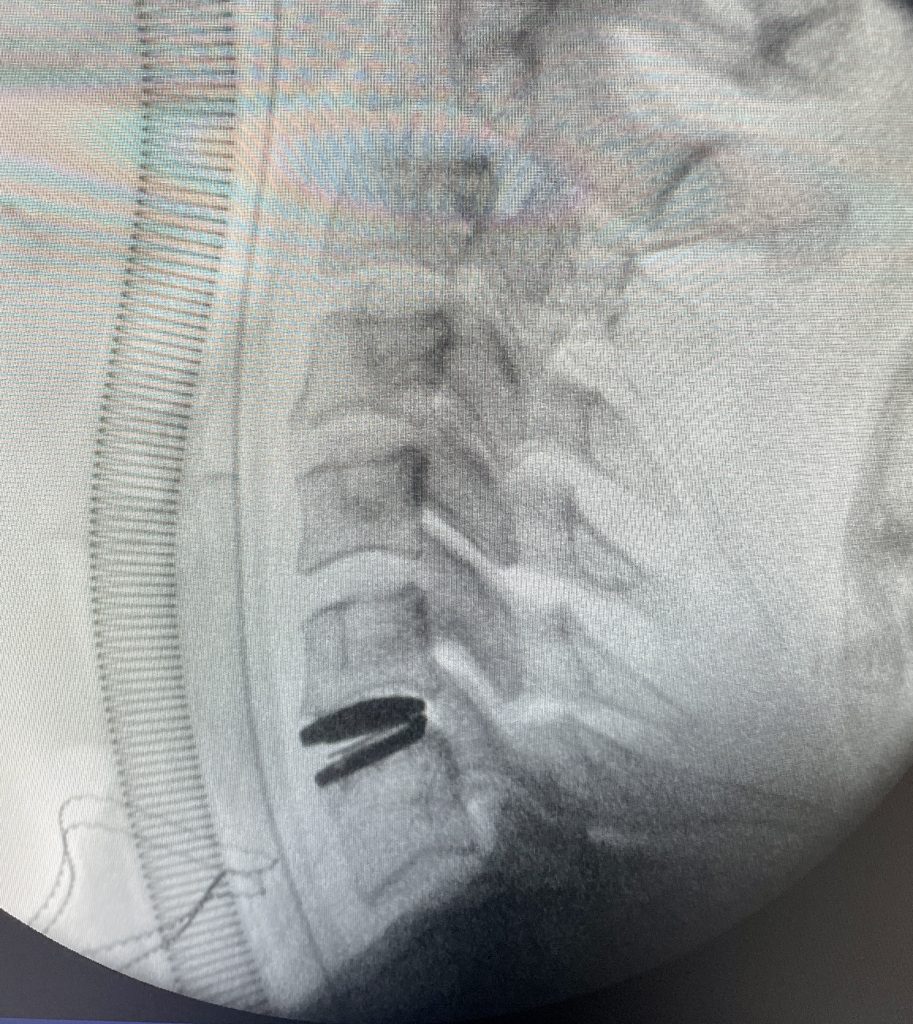

La cirugía puede realizarse en muchas ocasiones de modo mínimamente invasivo, utilizando el microscopio o apoyándonos en técnicas endoscópicas, por vía dorsal sin necesidad de resecar el disco cervical.

La cirugía de hernia cervical por vía posterior evita el uso de implantes y puede realizarse por técnicas mínimamente invasivas utilizando el microscopio o el endoscopio de columna, aunque la indicación está reservada a determinadas hernias con criterios concretos.